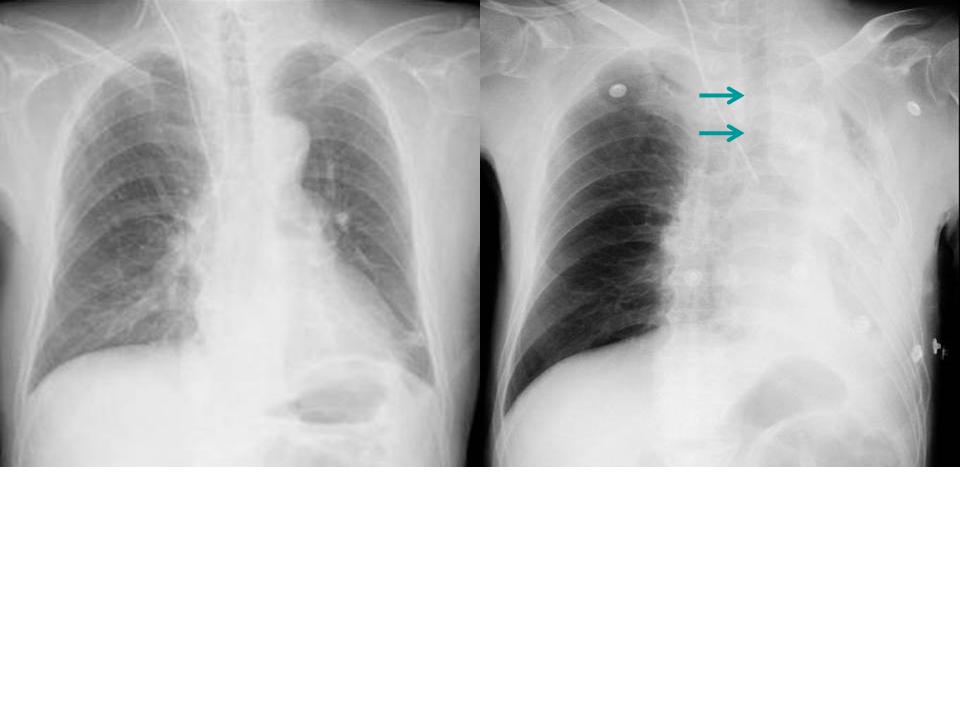

こちらを見て下さい。

わかりにくいかもしれませんが、このあたり。

気管が追いにくい、無くなっているようにも見えます。

CTで見ると…

3Dだと、こうなります。

気管狭窄ですね。こういう所見もレントゲンで捉えることができるのです。